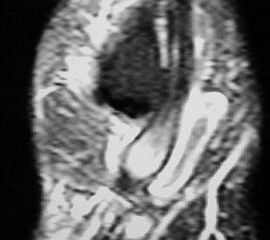

Unterbrechung des Retinakulums als indirektes Zeichen einer traumatischen Peronealsehnenluxation im MRT.

Abbildung 6

Neben der klinischen Untersuchung besitzt in der Diagnostik von Sehnenpathologie das MRT mit Kontrastmittel einen hohen Stellenwert 8910. Kontrastmittelaufnahme in die Sehne ist immer als Hinweis auf einen Riss zu werten. Weiterhin ist Flüssigkeit im Sehnengleitlager oder die Aufnahme von Kontrastmittel in das Sehnengleitgewebe ein indirektes Zeichen einer Sehnenpathologie.